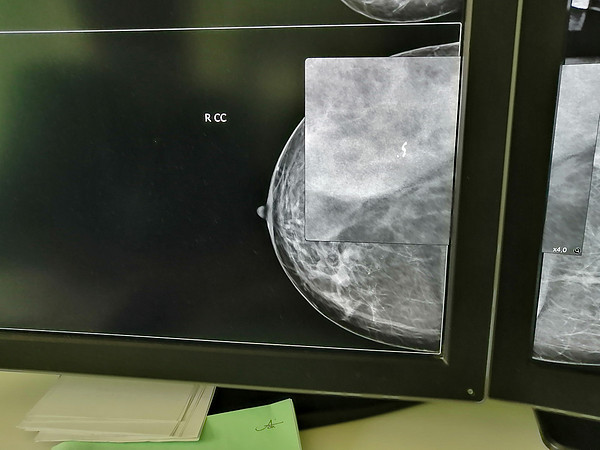

IMG_20210629_153113.